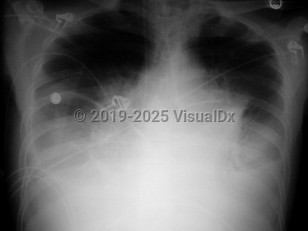

Inclusion criteria can be any one of the following: positive blood cultures, mediastinal adenopathy, or pleural effusions. The patient may also have nonspecific findings such as high fever, dyspnea, confusion, syncope, and nausea / vomiting. If diagnosed in this stage, the prognosis is still good if antibiotics are administered, pleural fluid is drained, and supportive care is provided.

Inclusion criteria can be one of the following: meningitis, respiratory failure (requiring mechanical ventilation), or shock. Findings from the previous stages may be concurrently present. In 2001, no patient who required mechanical ventilation and/or hemodynamic support survived. More recently, a critically ill patient who was exposed unintentionally did survive with critical care support.